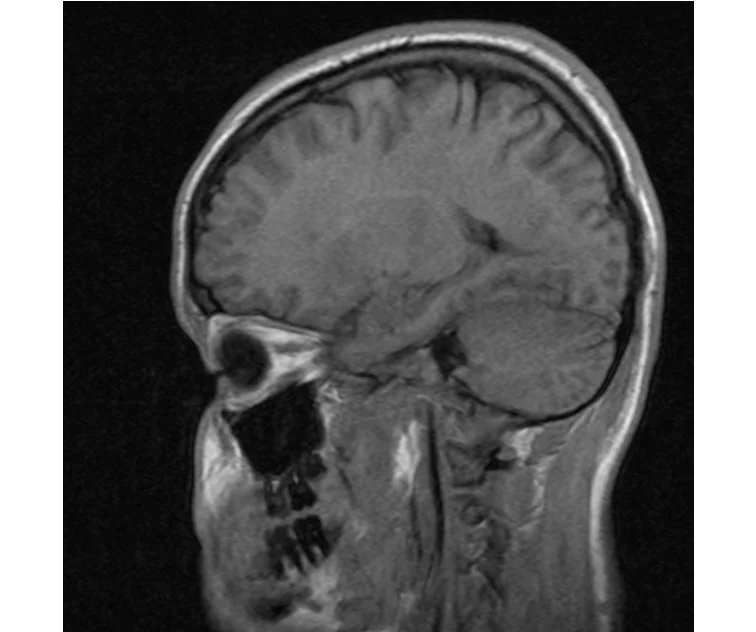

глянте на снимки томографии плиз

делал в обласной на siemense.В заключении выданом мне через 15мин.после мрт (легкая дегидрация)

Меня смутил факт выдачи заключения через 10мин(наверно они у них зарание напечатаные)я не медик.достаточно мимолётного взгляда на снимки?А вы видете на них гидроцефалию? Я лиш спросил куда идти с результатами томографии?и не хотел никого роздражать.

Я попросил взглянуть на снимки и сказать видна.ли на них гидроцефалия?или куда обратится за консультацией по этому вопросу?В мрт снимках наверно розбирается любой нервопатолог(я так предположил)

Я уже говорил, что независимо от того, есть на МРТ гидроцефалия или нет, лечиться тебе нужно только в том случае, если есть какие-либо проявления болезни, иначе на все эти анализы можешь забить... Но давай все-таки разберемся с томограммой.

Итак, с самого начала томограмма обозначала срез какого-либо органа на определенной глубине, позволяла заглянуть вовнутрь. При компьютерной томографии аппарат делает десятки срезов головного мозга в разных направлениях и из этого множества срезов он моделирует полноценное объемное изображение мозга в натуральную величину. Обрати внимание, компьютер работает не с этими миниатюрными изображениями, а с трехмерной моделью в масштабе 1:1. Эту модель вдоль и поперек анализирует суперсовременный компьютер, выполняющий миллионы операций в секунду. Только ***** может пытаться перепроверить компьютер, ведь человеку не хватит всей жизни чтобы проанализировать то, что компьютер с тобой сделал за 10 минут. Я хочу, чтобы ты это понял!

Ты разместл здесь несколько миниатюр и хочешь, чтобы врач по ним создал полноценное объемное изображение в натуральную величину, а потом осмотрел его со всех сторон и дал заключение? Но ведь это невозможно. Это просто насмешка над врачом, это издевательство над здравым смыслом. Принеси Букеру уменьшенный в 50 раз снимок зуба и спроси у него, в каком состоянии там корневые каналы. Или давай я дам тебе скрин со спутниковой карты города и попрошу тебя описать, какого цвета и какой модели запечатленная со спутника машина, какой у нее гос.номер, сколько в ней пассажиров, сколько из них мужчин и сколько женщин...